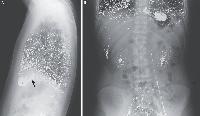

Мобильный рентгенаппарат + оцифровщик. Получение рентгеновского изображения на экране ноутбука. Вариант за 1,4 миллиона рублей под ключ.

Мобильный рентгенаппарат с печатью рентгенограмм на рентгеновской пленке. Цена 700000 рублей.

В случае перелома шейки бедра компания МосРентген Центр госпитализирует в Склиф для эндопротезирования.